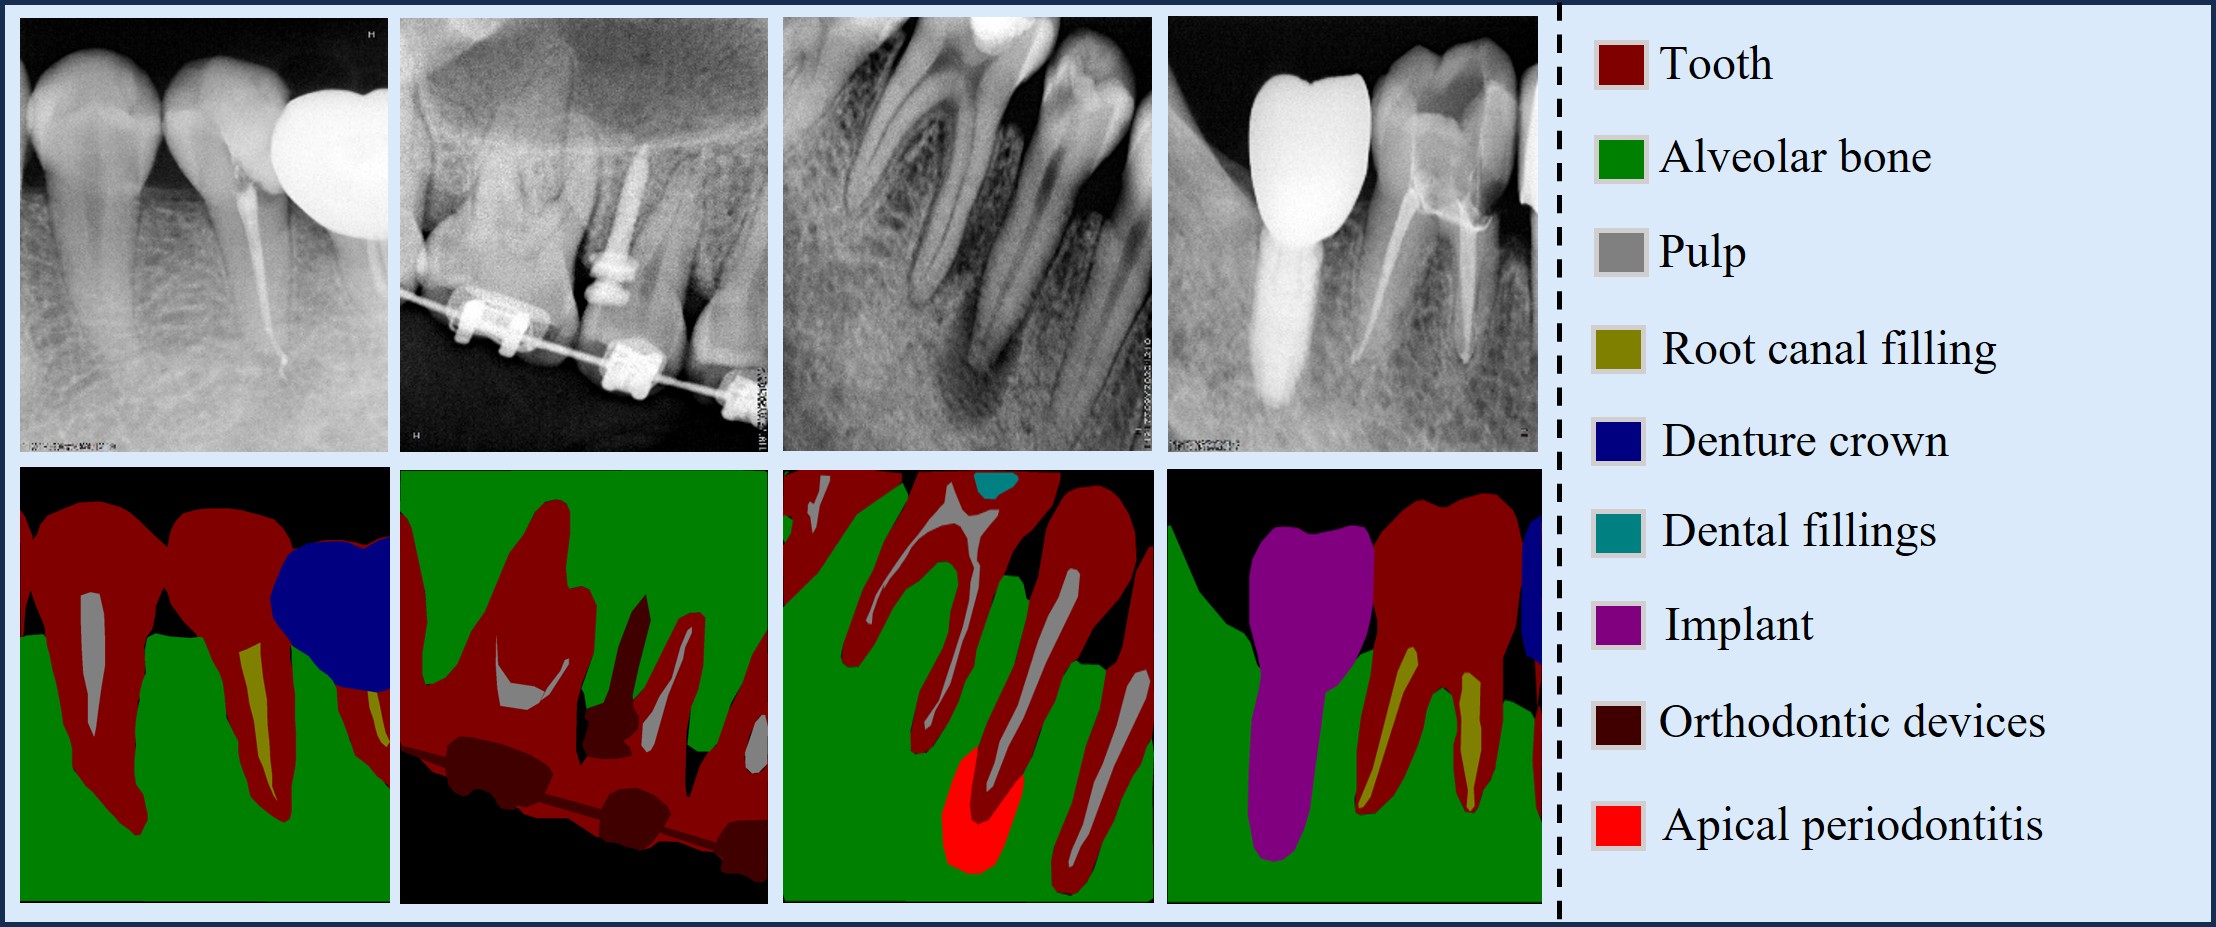

In Table 1, PRAD-10K is compared with some existing 2D dental datasets. Most prior datasets are small and focus on PAN or occlusal and intraoral radiographs, highlighting a gap in large-scale PR datasets. The introduction of PRAD-10K provides a benchmark for the application of DL in the analysis of PR images. Fig. 2 shows four PRAD-10K images with expert pixel-level annotations, covering all category labels. On the right side of Fig. 2, a detailed label index is provided. PRAD-10K includes nine types of pixel-level annotations for anatomical structures, lesions, and restorations or devices. Additionally, classification labels are provided for some images with periodontitis, apical periodontitis, or inadequate root canal fillings.

Refer to caption

Figure 2: Examples from the PRAD-10K dataset (top left) along with their corresponding pixel-level annotations (bottom left). The right side displays the label distribution.